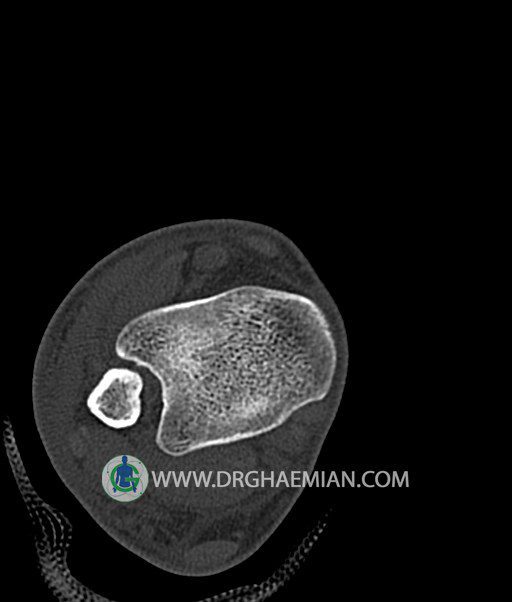

سی تی اسکن پا تصاویری عرضی از پا ایجاد می کند. این روش تصویربرداری از اشعه ایکس برای ایجاد تصاویر ایجاد می شود. در این کیس هيپرپلازي مچ پا، تورم نسج نرم و استئوفیت در مچ پا بیمار مشاهده می شود.

سي تي اسکن مچ پاي راست (مولتي ديدکتور 16 با مقاطع ظريف و بازسازي هاي ساژيتال و کرونال و 3D):

– تورم نسج نرمي در اطراف قوزک خارجي پاي راست

– Cortical Fx در قسمت خلفي اپيفيز ديستال تيبيا و

– هيپرپلازي lateral tubercle در تالوس ( stieda process ) همراه با اوستئوفيت در لبه

مديال تيبيا و تالوس